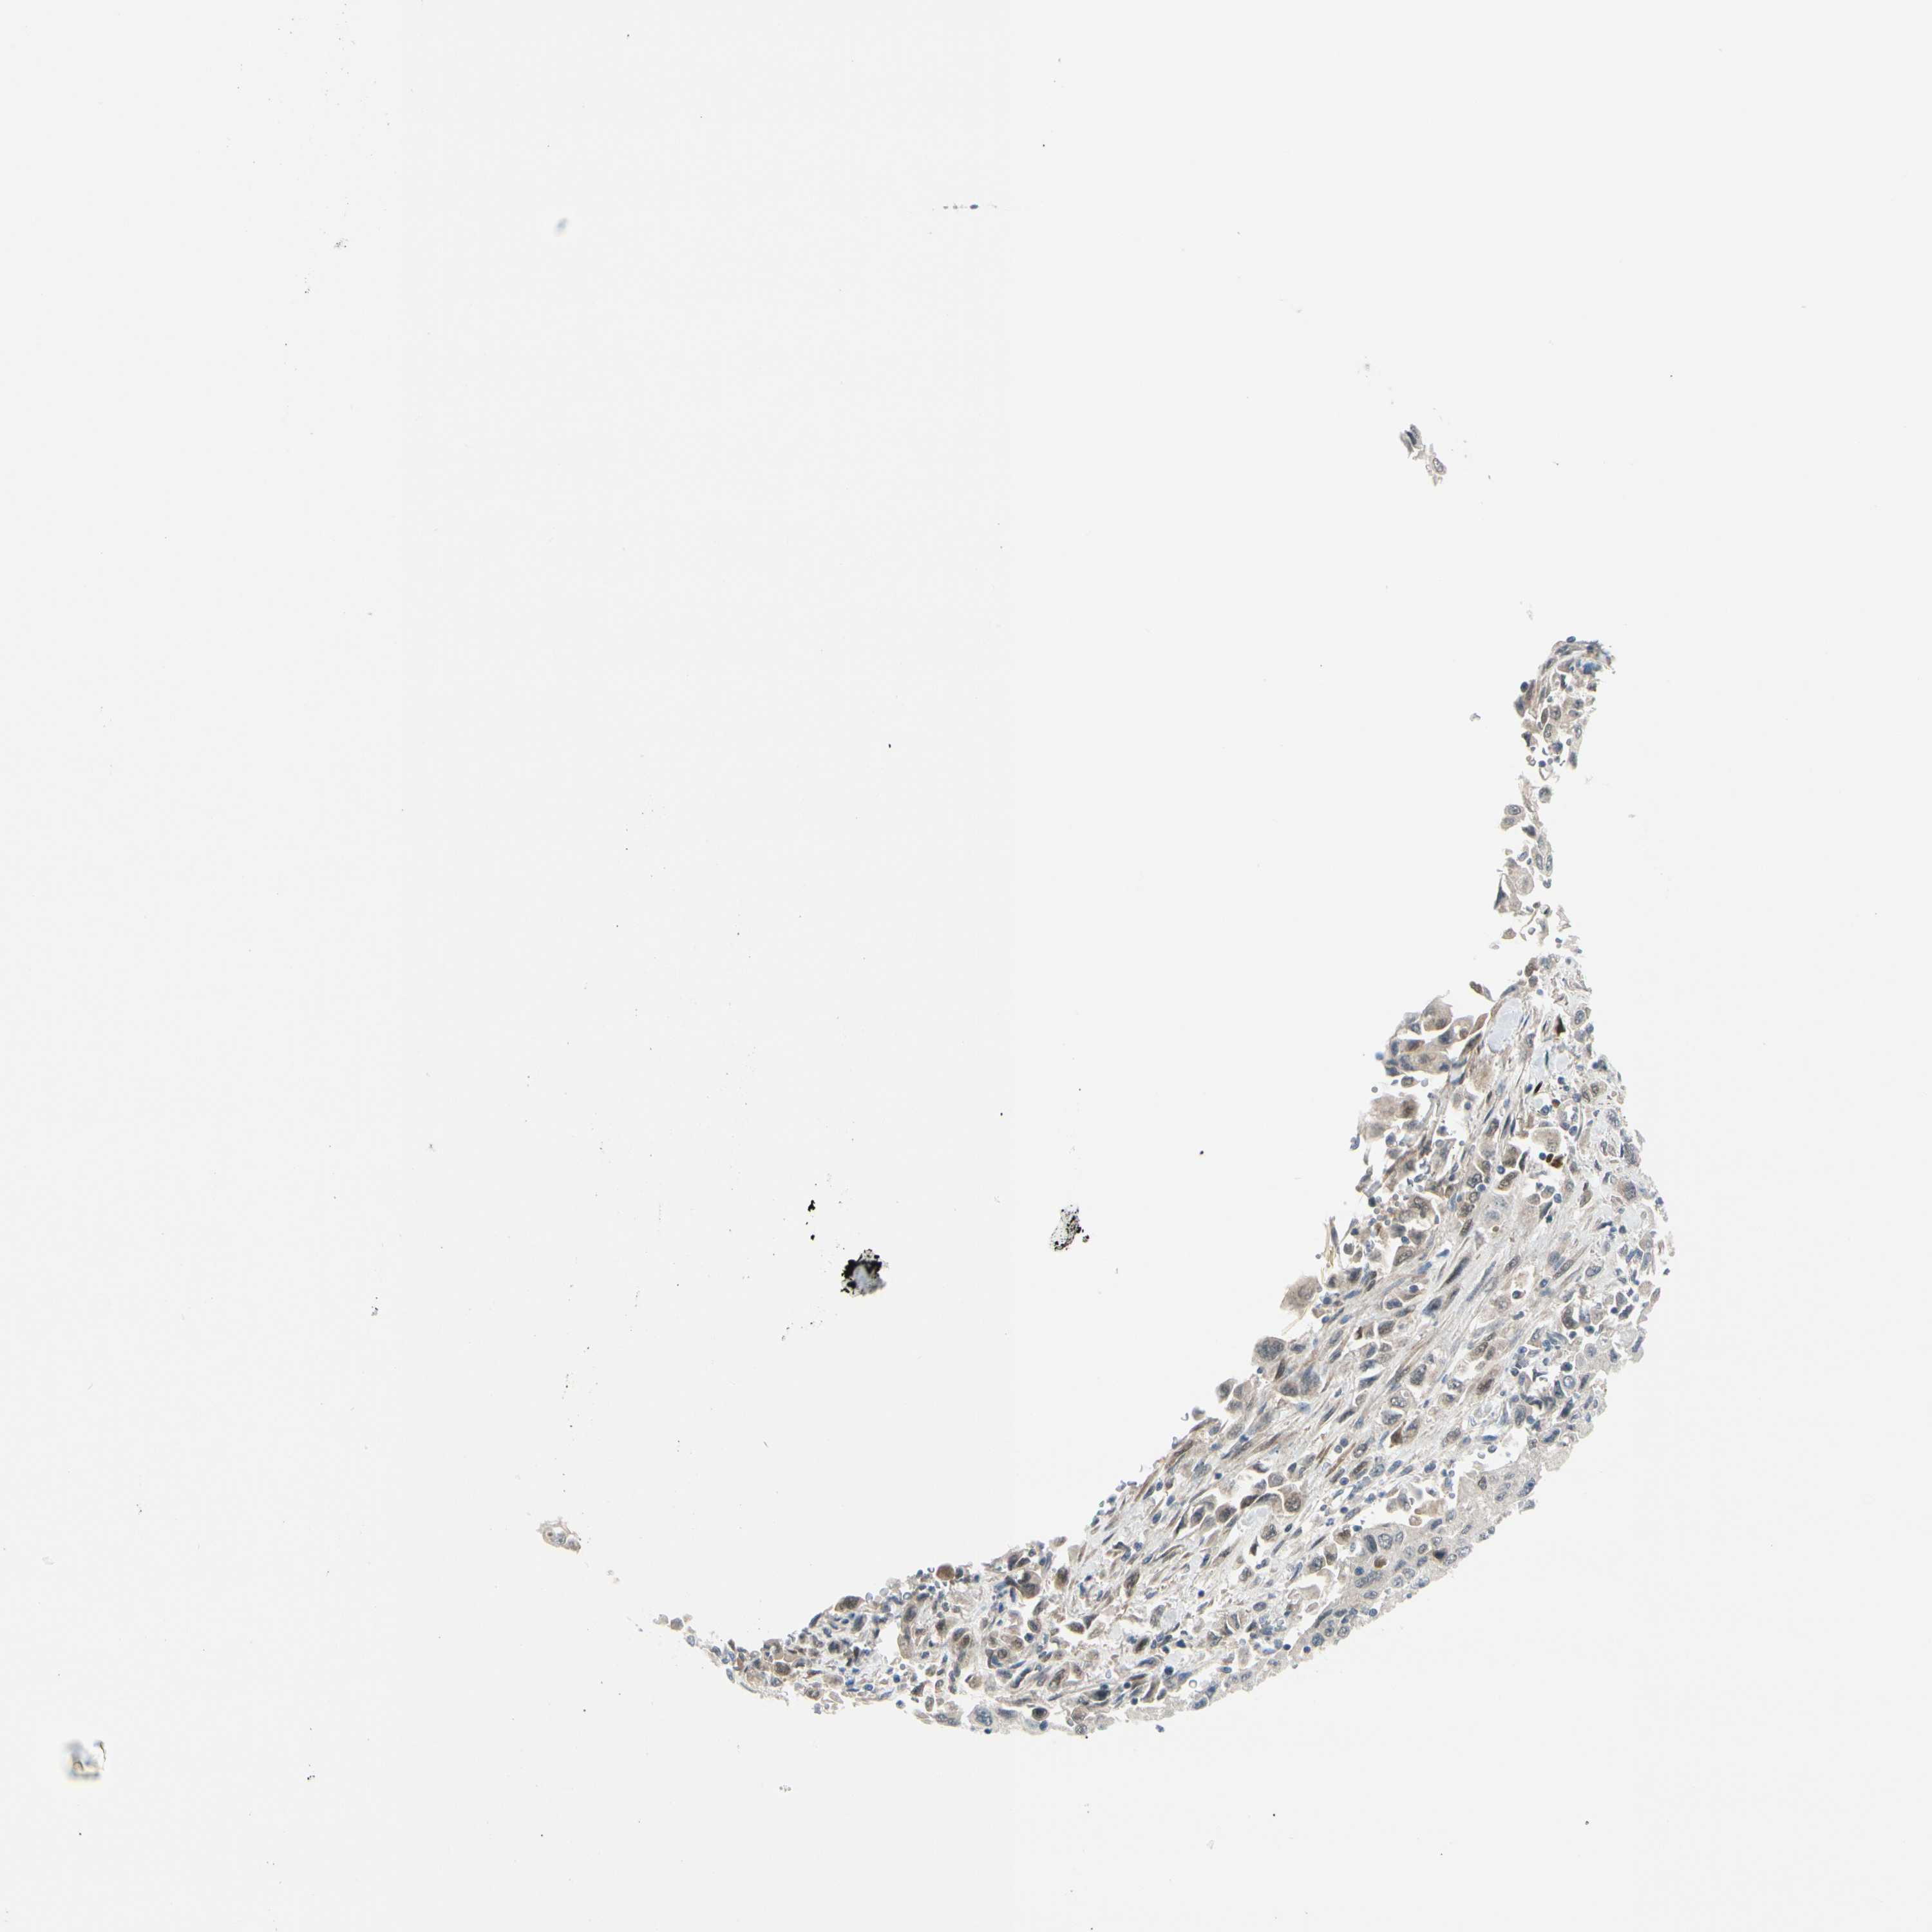

PANCREATIC CANCER - Protein expressioni

A mouse-over function shows sample information and annotation data. Click on an image to view it in a full screen mode. Samples can be filtered based on level of antibody staining by selecting one or several of the following categories: high, medium, low and not detected. The assay and annotation is described here.

Note that samples used for immunohistochemistry by the Human Protein Atlas do not correspond to samples in the TCGA dataset.

Antibody stainingi

Antibody staining in the annotated cell types in the current human tissue is reported as not detected, low, medium, or high, based on conventional immunohistochemistry profiling in selected tissues. This score is based on the combination of the staining intensity and fraction of stained cells.

Each image is clickable and will lead to virtual microscopy that enables deeper exploration of all samples and also displays staining intensity scores, fraction scores and subcellular localization as well as patient and tissue information for each sample.

Antibody HPA005922

Antibody HPA006028

Antibody CAB008368

Staining

High

Medium

Low

Not detected

Intensity

Strong

Moderate

Weak

Negative

Quantity

>75%

75%-25%

<25%

None

Location

Nuclear

Cytoplasmic/membranous

Cytoplasmic/membranous,nuclear

Adenocarcinoma, NOS

Adenocarcinoma, metastatic, NOS